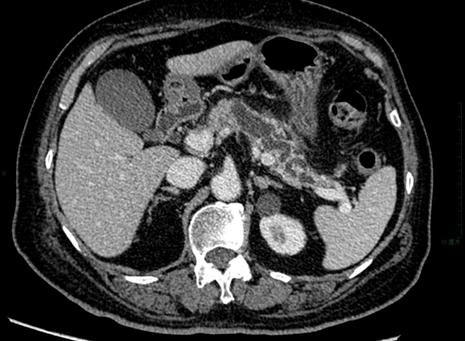

这种疾病的95%以上见于年轻女性,属低度恶性或潜在恶性倾向,其肿瘤边界清楚,有包膜,平均直径8-9cm,内部是实性成分和囊性成分混杂在一起,SCT由于容易合并出血,内部发生坏死的频率很高,在30%的肿瘤边缘可出现圆弧状或蛋壳状钙化,20%的囊性成分中伴有出血。

SCT多见于年轻女患者

胰腺实性假乳头状瘤的CT表现特征为:增强后实性成分呈渐进性强化,实性成分可表现为“浮云”征或呈附壁结节,或表现为囊实性相间分布,其中以实性成分为主者,囊性成分多位于包膜下,很多病灶具有明显完整光滑的包膜,且强化明显。

SCT的CT特征比较典型